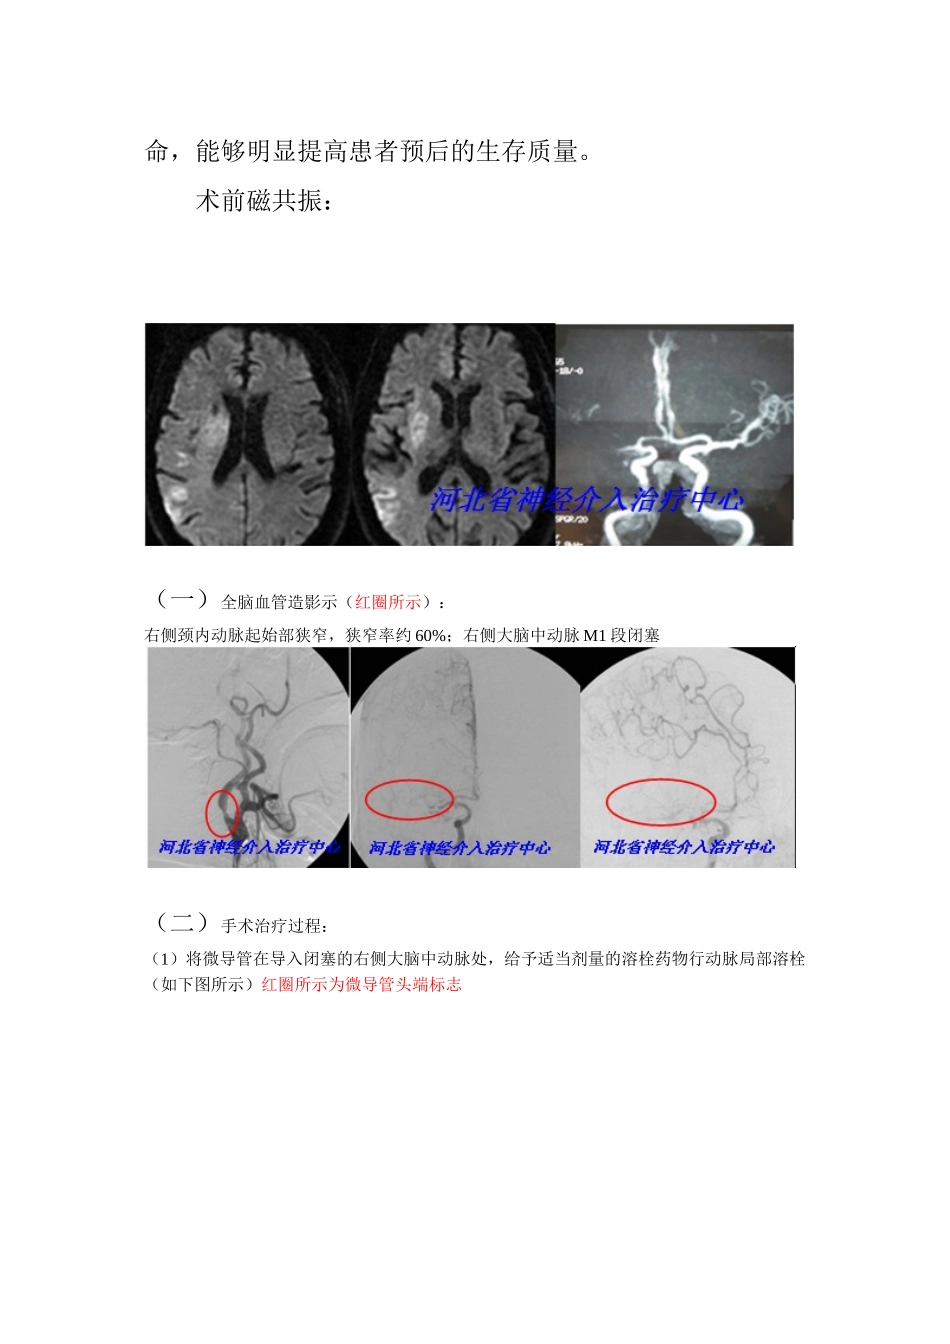

脑动脉瘤+神经介入治疗——记河北医大一院神经外科(河北省神经介入治疗中心)开通脑血管病绿色通道积极抢救急性脑栓塞患者张老汉,67岁,于2013-07-2618:30左右在家干活时患者突然出现言语含糊不清,并伴左侧肢体不能活动的症状,由家人急呼“120”送至医大一院急诊科,行头颅CT显示:未见明显异常。请神经外科会诊,初步考虑wei急性脑缺血症状,立即收住院治疗,急查头颅磁共振提示:右侧额、颞、顶、岛叶及右侧基底节脑缺血(急性期);右侧大脑中动脉闭塞。给予对症处理,并立即向候凯主任医师汇报,侯主任分析病情:考虑患者为急性脑栓塞,指示争取在溶栓时间窗上限的6小时内行介入溶栓手术治疗,积极抢救生命。管床医生立即向家属交代患者目前病情及手术相关事宜和手术风险,家属经过再三的商榷后,同意手术治疗。此时已是19:30,立即开通脑血管病绿色通道,通知导管室及麻醉科医生,于19:50患者推往导管室行全脑血管造影,20:20全脑血管造影结束,提示:右侧大脑中动脉M1段闭塞,右侧颈内动脉起始部狭窄,狭窄率约60%。向家属交代病情后,立即决定行右侧大脑中动脉血管闭塞处局部溶栓再通术、右侧大脑中动脉狭窄处球囊扩张术、支架置入术。由于患者血管硬化较明显,经过多次尝试指引导管无法导入颈总动脉,候凯教授果断决定放弃股动脉途径,立即改用右侧颈总动脉途径,要争分夺秒抢救患者。由于患者右侧颈内动脉起始部有约60%的狭窄,操作不慎,随时会使狭窄处的斑块脱落造成远端血管新的栓塞,难度和风险都非常高,而且时间非常急迫,过了6小时的治疗时间窗患者就是去了治疗的意义。时间不等人,候凯教授及神经外科的医生们经过快速缜密的讨论后,成功为患者实施了右侧大脑中动脉血管闭塞处局部溶栓再通术、右侧大脑中动脉狭窄处球囊扩张术、支架置入术,此时为22:30,距患者发病约4小时。张老汉于第二天早晨神志转清,言语较流利,左侧肢体可按吩咐做简单活动,患者病情在进一步的恢复中。河北医科大学第一医院神经外科暨河北省神经介入治疗中心主任候凯教授指出,目前全世界的脑血管病患者以约200万人/年的速度递增,已经成为造成人类死亡的第一因素,其中缺血性脑卒中高达75%~85%。尤其是老年人及“三高”人群。需要引起社会及广大老百姓的高度注意。而对于急性脑栓塞的患者,一般在急性发病期头颅CT无明显异常表现,很容易被误诊误治,需尽快送至正规的经验丰富的大型神经介入治疗中心明确诊断,尽可能在溶栓时间窗内行快速的专业化治疗,在最短的时间内积极抢救生命,能够明显提高患者预后的生存质量。术前磁共振:(一)全脑血管造影示(红圈所示):右侧颈内动脉起始部狭窄,狭窄率约60%;右侧大脑中动脉M1段闭塞(二)手术治疗过程:(1)将微导管在导入闭塞的右侧大脑中动脉处,给予适当剂量的溶栓药物行动脉局部溶栓(如下图所示)红圈所示为微导管头端标志(2)使用微导丝行闭塞血管再通术(如下图所示)微导管在微导丝的引导下逐步通过局部闭塞血管,到达远端,实现闭塞血管再通。红圈所示为局部闭塞狭窄的血管(3)行右侧大脑中动脉狭窄处球囊扩张术、支架置入术(如下图所示)球扩支架充盈中的球囊河北省神经介入治疗中心河北省神经介入治疗中心河北省神经介入治疗中心河北省神经介入治疗中心河北省神经介入治疗中心河北省神经介入治疗中心河北省神经介入治疗中心河北省神经介入治疗中心(三)行右侧大脑中动脉血管闭塞处局部溶栓再通术、右侧大脑中动脉狭窄处球囊扩张术、支架置入术后复查造影(如下图所示)